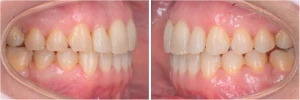

CAS 4 : Orthodontie de l’enfant - Encombrement et supraclusion - Le stripping

Cette jeune patiente présente un encombrement sévère à l’arcade inférieure (mandibule). De plus, elle présente un recouvrement total des incisives mandibulaires par les incisives maxillaires (supraclusion totale).

Ici, l’alignement dentaire a pu être réalisé grâce à l’utilisation de « stripping » ou réduction amélaire interproximale (RIP). Ce procédé consiste en la réduction de la largeur de la dent à l’aide de fraises ou de petites bandelettes abrasives. Cette réduction est réalisée sous aide optique afin de rester le moins délabrante possible. Seule une fine couche d’émail (partie dure de la dent) est retirée.

Les espaces libérés par cette technique, en association avec une reconformation d’arcade (élargissement de la forme globale du sourire) nous ont permis d’aligner les dents de notre patiente et de corriger son sourire.